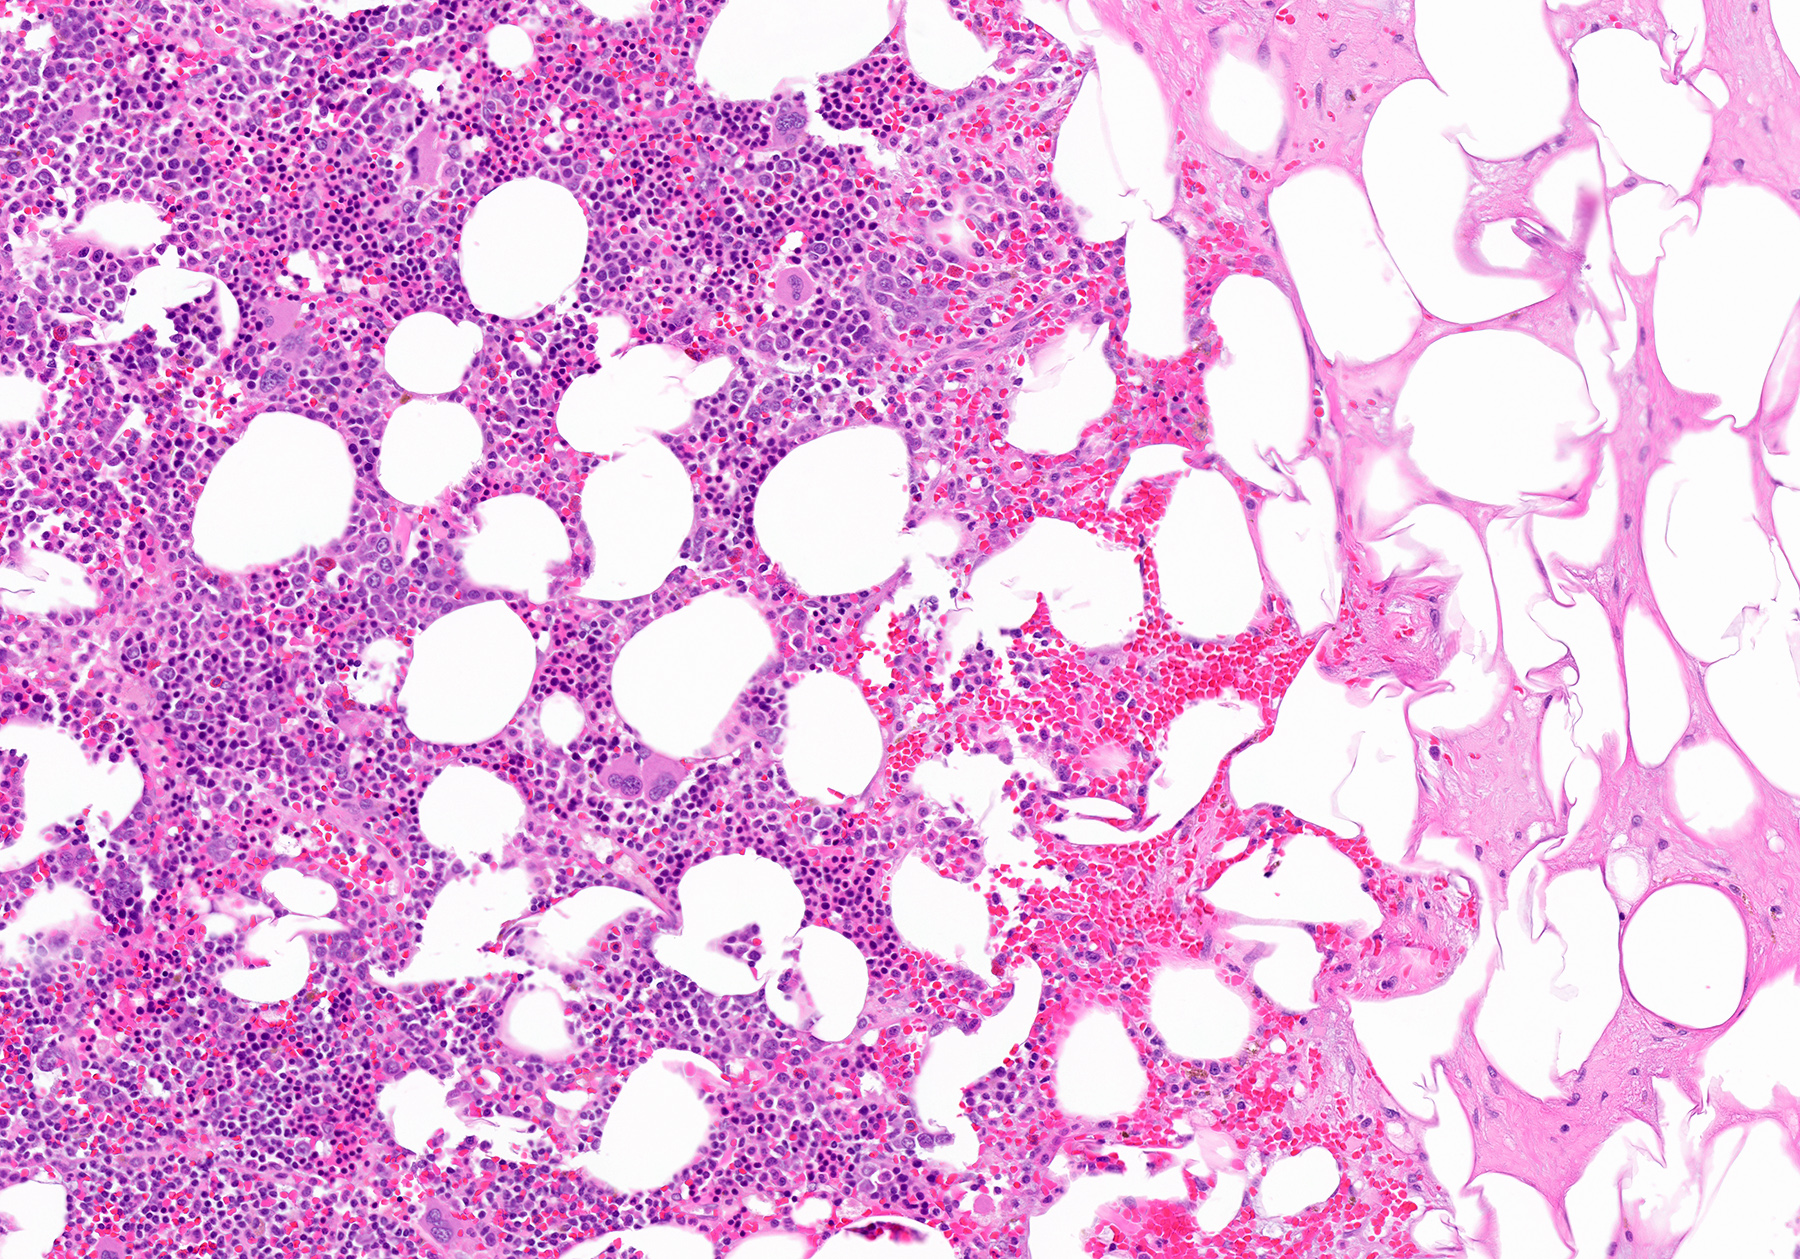

Microscopic (histologic) description

- Mixture of mature adipocytes and extramedullary trilineage hematopoietic cells with full maturation (similar to a hypercellular bone marrow) but often with a markedly increased number of megakaryocytes (Am J Surg Pathol 2006;30:838)

- Calcification, osseous metaplasia and fibrosis can occur

- Rarely may have areas of fibromyxoid degeneration resembling low grade fibromyxoid sarcoma

- Can develop in combination with adrenal cortical tumors, ganglioneuroma, hibernoma, bilateral macronodular adrenocortical disease and congenital adrenal hyperplasia

Microscopic (histologic) images

Contributed by Debra L. Zynger, M.D., Anil Parwani, M.D., Ph.D., O. Hans Iwenofu, M.D., Ph.D. and @ThatGlassTho on Twitter